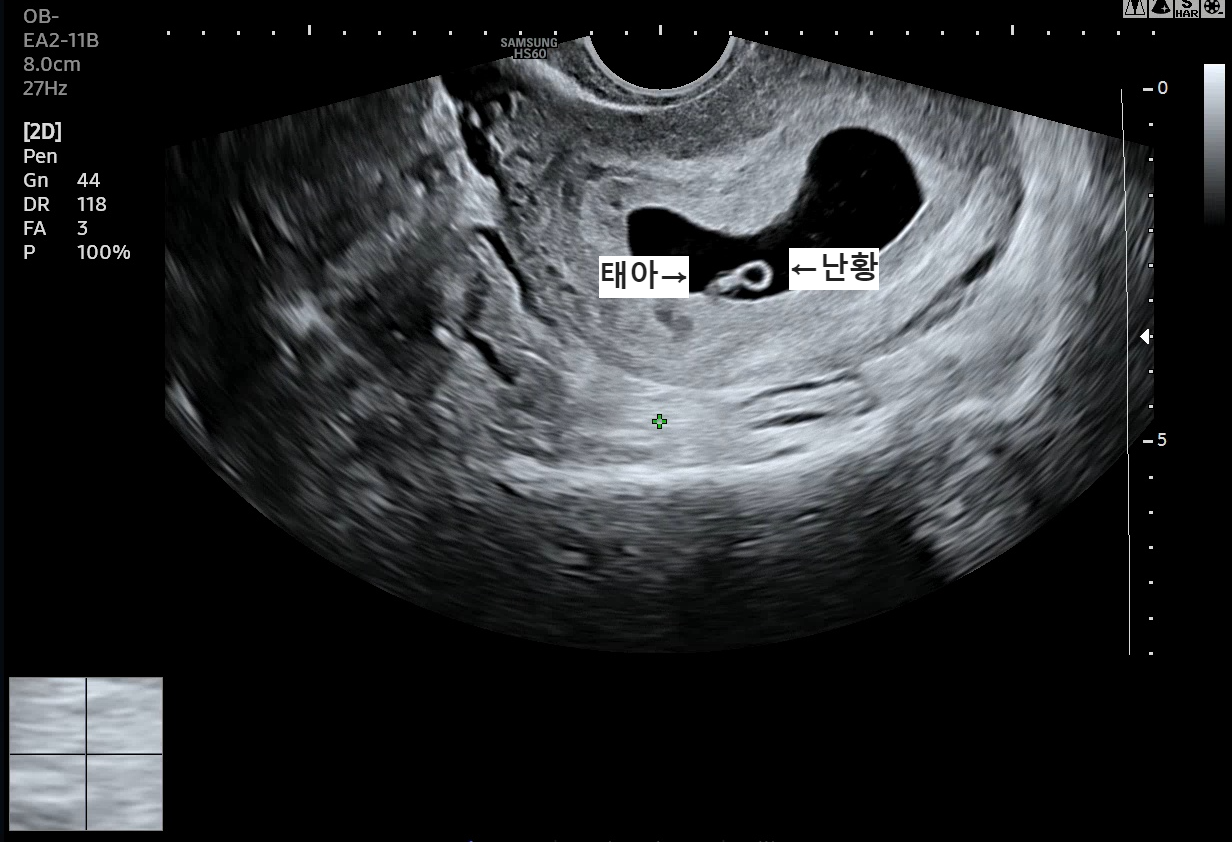

무사히 난황과 태아가 확인이 되었다!

처음에는 큰 동그라미가 태아의 머리인줄 알았는데 거긴 난황이고 태아는 난황옆에 조그마하게 붙어있는게 태아라고 한다. 지금 태아의 크기는 5mm라고 하니 2주전에 아기집의 크기와 똑같은 크기!

심장이 있어서 심장소리도 들을 수 있는데 아직 아기가 크지않아서 심장박동수가 120bpm정도지만, 더 크면 160 ~ 100bpm정도 된다고 하셨다.

초음파 화면으로 심장이 뛰는것도 확인 할 수 있었는데 깜빡깜빡하는게 심장이라고 한다..!!